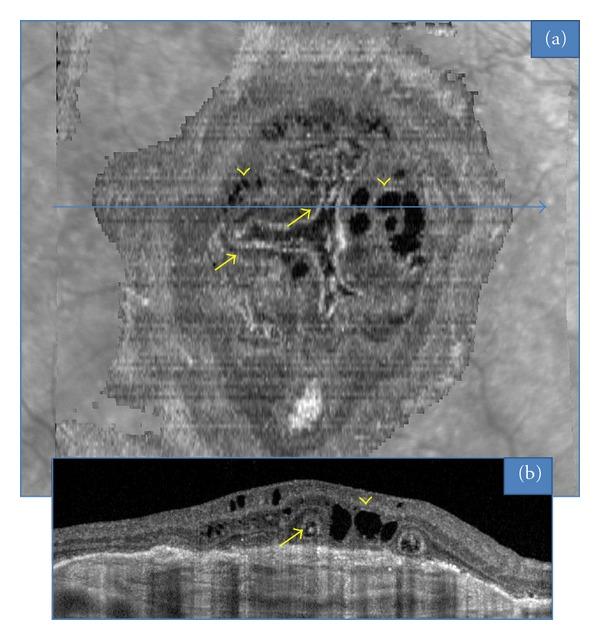

Purpose. "En face" is an emerging imaging technique derived from spectral domain optical coherence tomography (OCT). It produces frontal sections of retinal layers, also called "C-scan OCT." Outer retinal tubulations (ORTs) in age-related macular degeneration (AMD) are a recent finding evidenced by spectral-domain OCT. The aim of this study is to characterize the morphology of ORT according to the form of AMD, using "en-face" spectral domain OCT. Methods. "En face" OCT imaging was prospectively performed in 26 consecutive eyes with AMD that also had ORT. Results. There were 15 neovascular, 8 atrophic, and 3 eyes with a mixed (fibrotic and atrophic) form of AMD. Among the neovascular group, the most frequent tubulation pattern on "en-face" OCT was a branching network emanating from a fibrovascular scar; we term this pattern as "pseudodendritic." It did not require treatment when observed as an isolated finding. In all cases of atrophic AMD, the tubular network was located at the edge of the geographic atrophy area, and formed a "perilesional" pattern. Six atrophic cases showed tubular invaginations inside this area. Conclusion. "En face" OCT is a valuable technique in the diagnosis and followup of macular disease. It revealed the main characteristic patterns of ORT associated with neovascular and atrophic AMD.

目的。“正面成像”是一种源自光谱域光学相干断层扫描(OCT)的新兴成像技术。它能生成视网膜各层的正面图像,也称为“C 扫描 OCT”。年龄相关性黄斑变性(AMD)中的视网膜外层微管(ORTs)是光谱域 OCT 最近发现的现象。本研究的目的是使用“正面成像”光谱域 OCT 根据 AMD 的类型来描述 ORT 的形态。方法。对 26 只连续患有 AMD 且伴有 ORT 的眼睛进行前瞻性“正面成像”OCT 成像。结果。有 15 只新生血管性、8 只萎缩性以及 3 只混合性(纤维化和萎缩性)AMD 眼睛。在新生血管性组中,“正面成像”OCT 上最常见的微管模式是从纤维血管瘢痕发出的分支网络;我们将这种模式称为“假树枝状”。当作为孤立发现观察时不需要治疗。在所有萎缩性 AMD 病例中,管状网络位于地图样萎缩区域的边缘,并形成“病灶周围”模式。6 例萎缩性病例在该区域内显示有管状内陷。结论。“正面成像”OCT 是黄斑疾病诊断和随访中的一项有价值的技术。它揭示了与新生血管性和萎缩性 AMD 相关的 ORT 的主要特征模式。